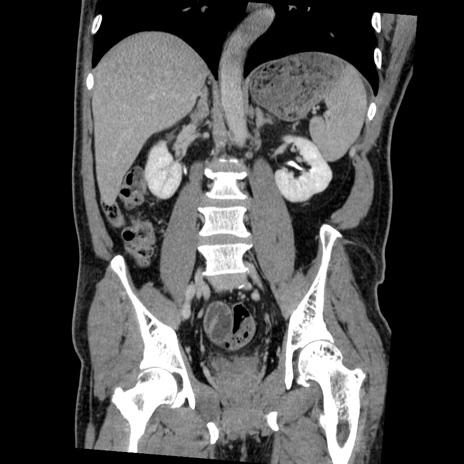

症例22(冠状断像)

【症例】50歳代男性

【主訴】腹痛

【現病歴】AVMからの被殻出血のため回復期リハ病棟入院中。 本日午後3時頃急に下腹部痛が出現した。

【既往歴】AVM、被殻出血、虫垂炎、高血圧

【身体所見】意識晴明、左半身不全麻痺、会話の理解は良好、36.5°C、腹部:膨隆、全体に板状硬、下腹部正中に圧痛点あり、反跳痛-、筋性防御不明、右下腹部にope scar

【データ】WBC 9400、CRP 0.06